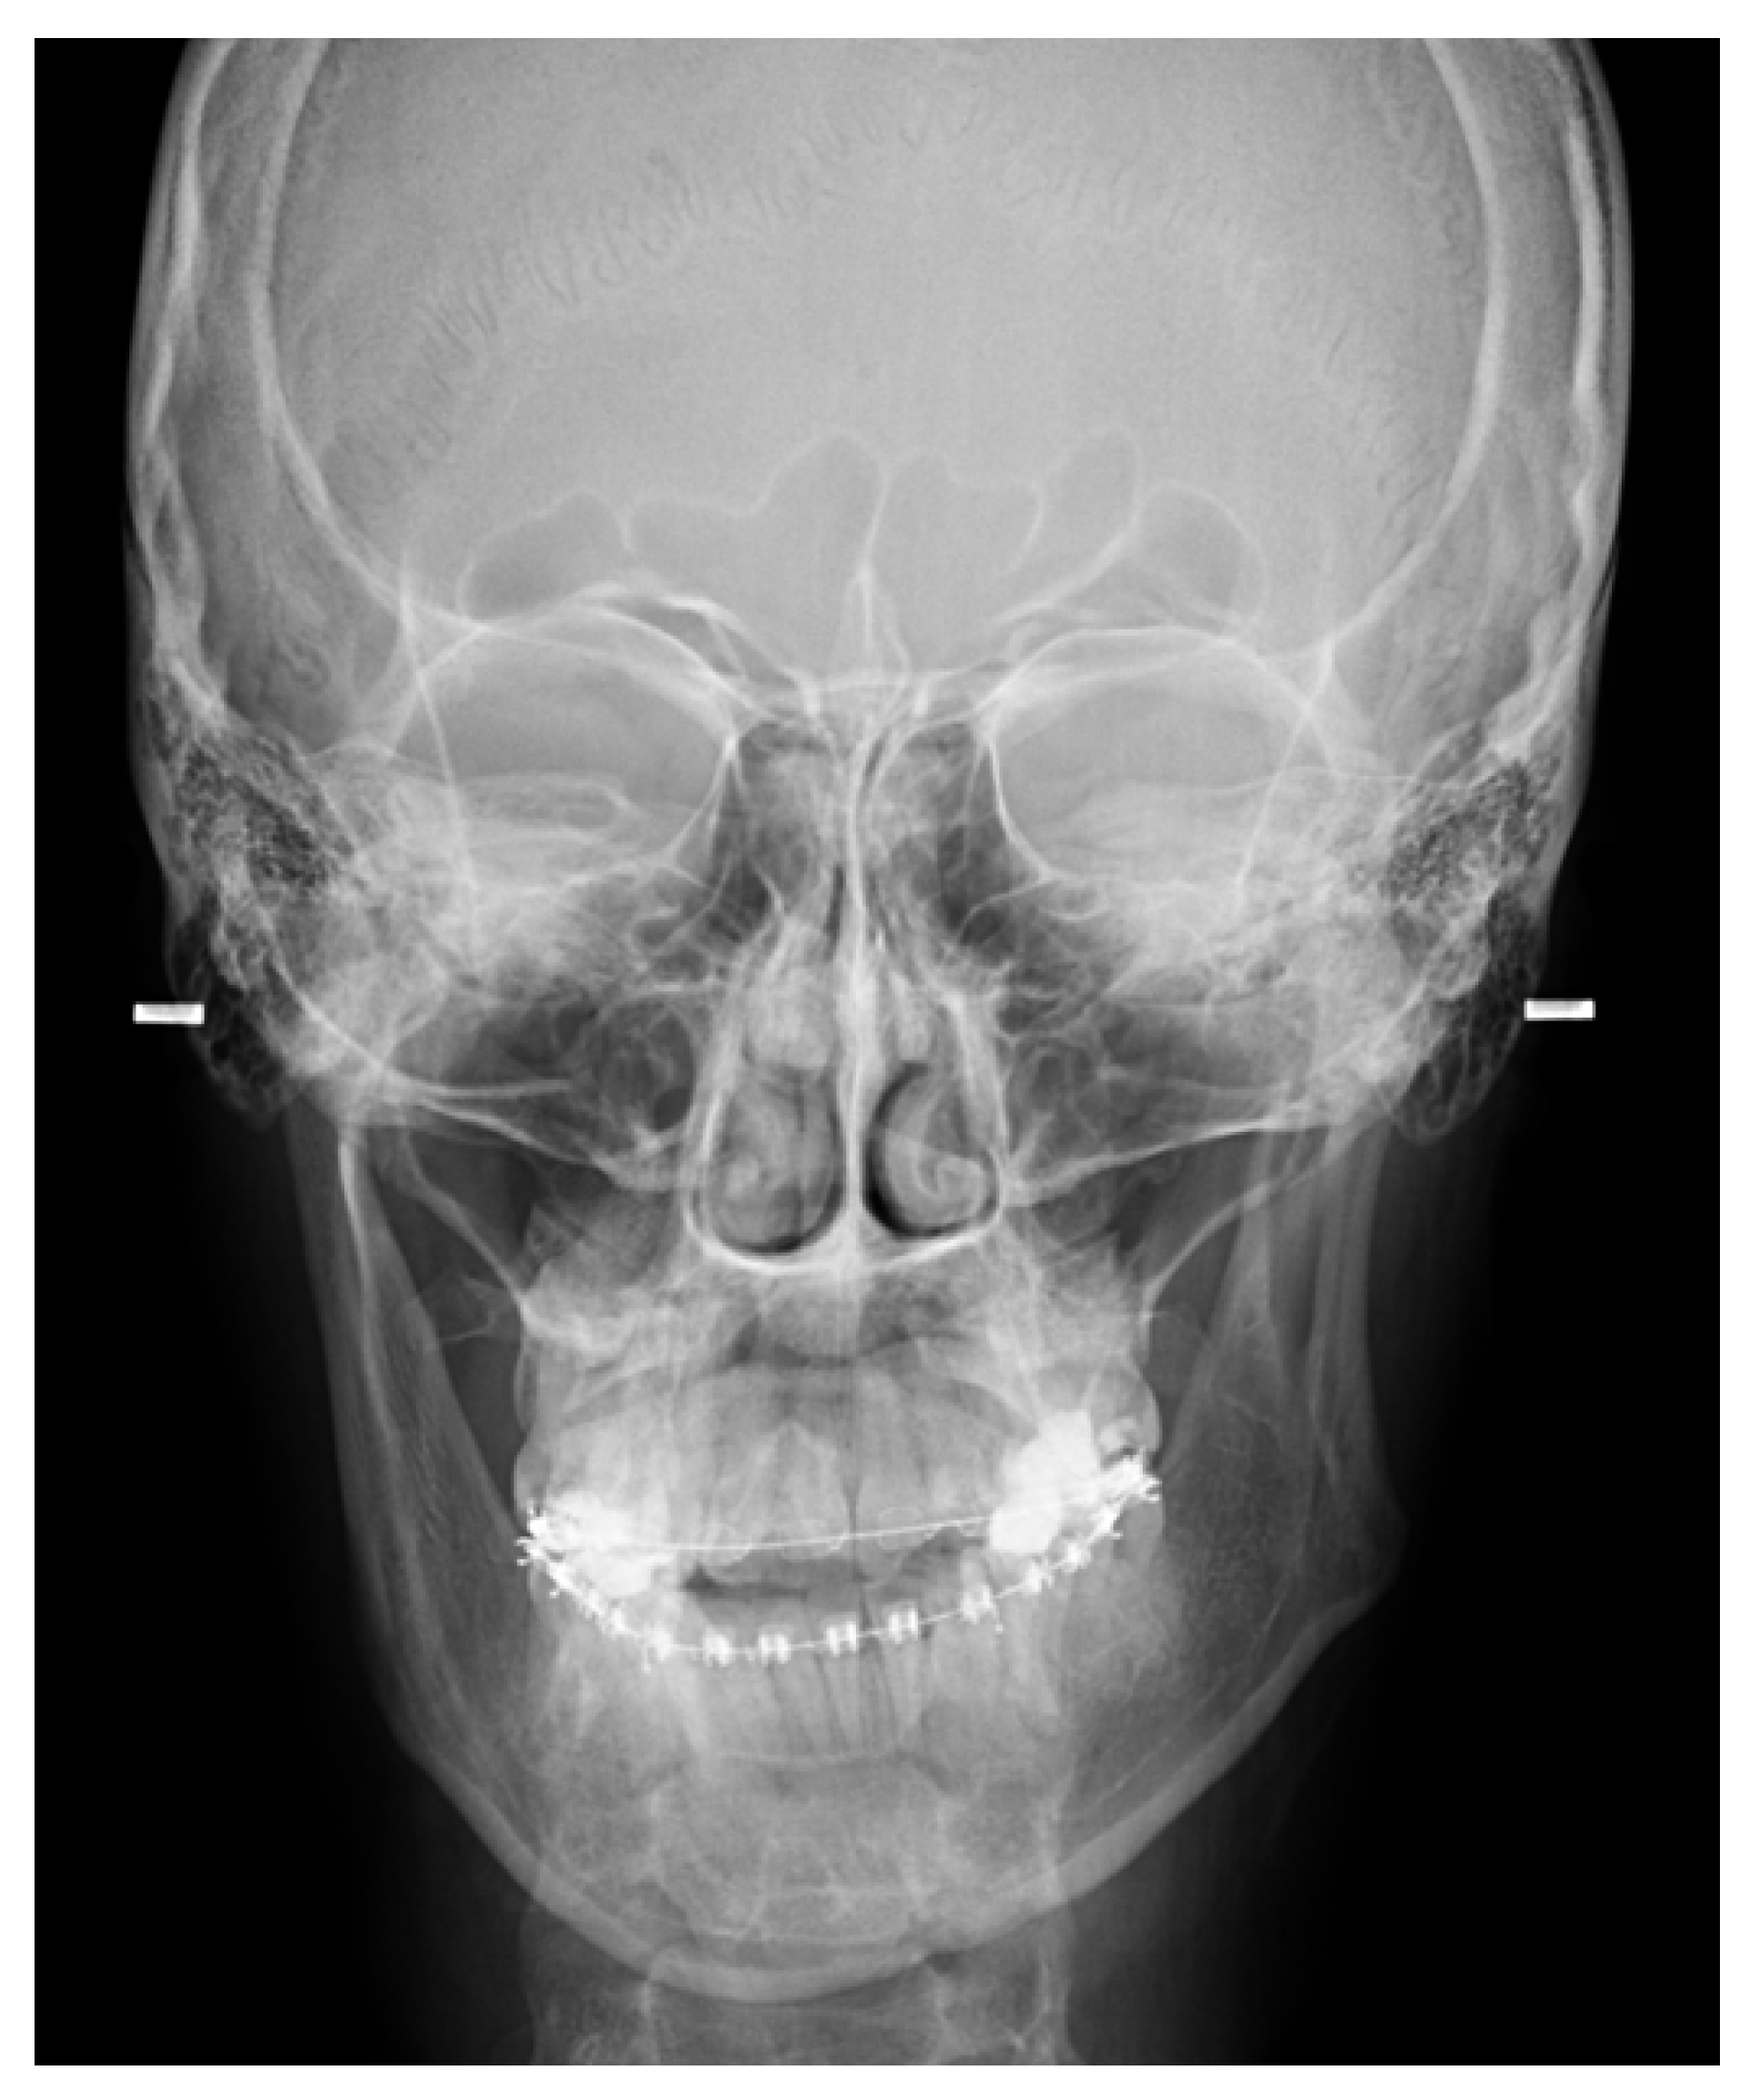

5.1. Panoramic Radiographs and Computed Tomography